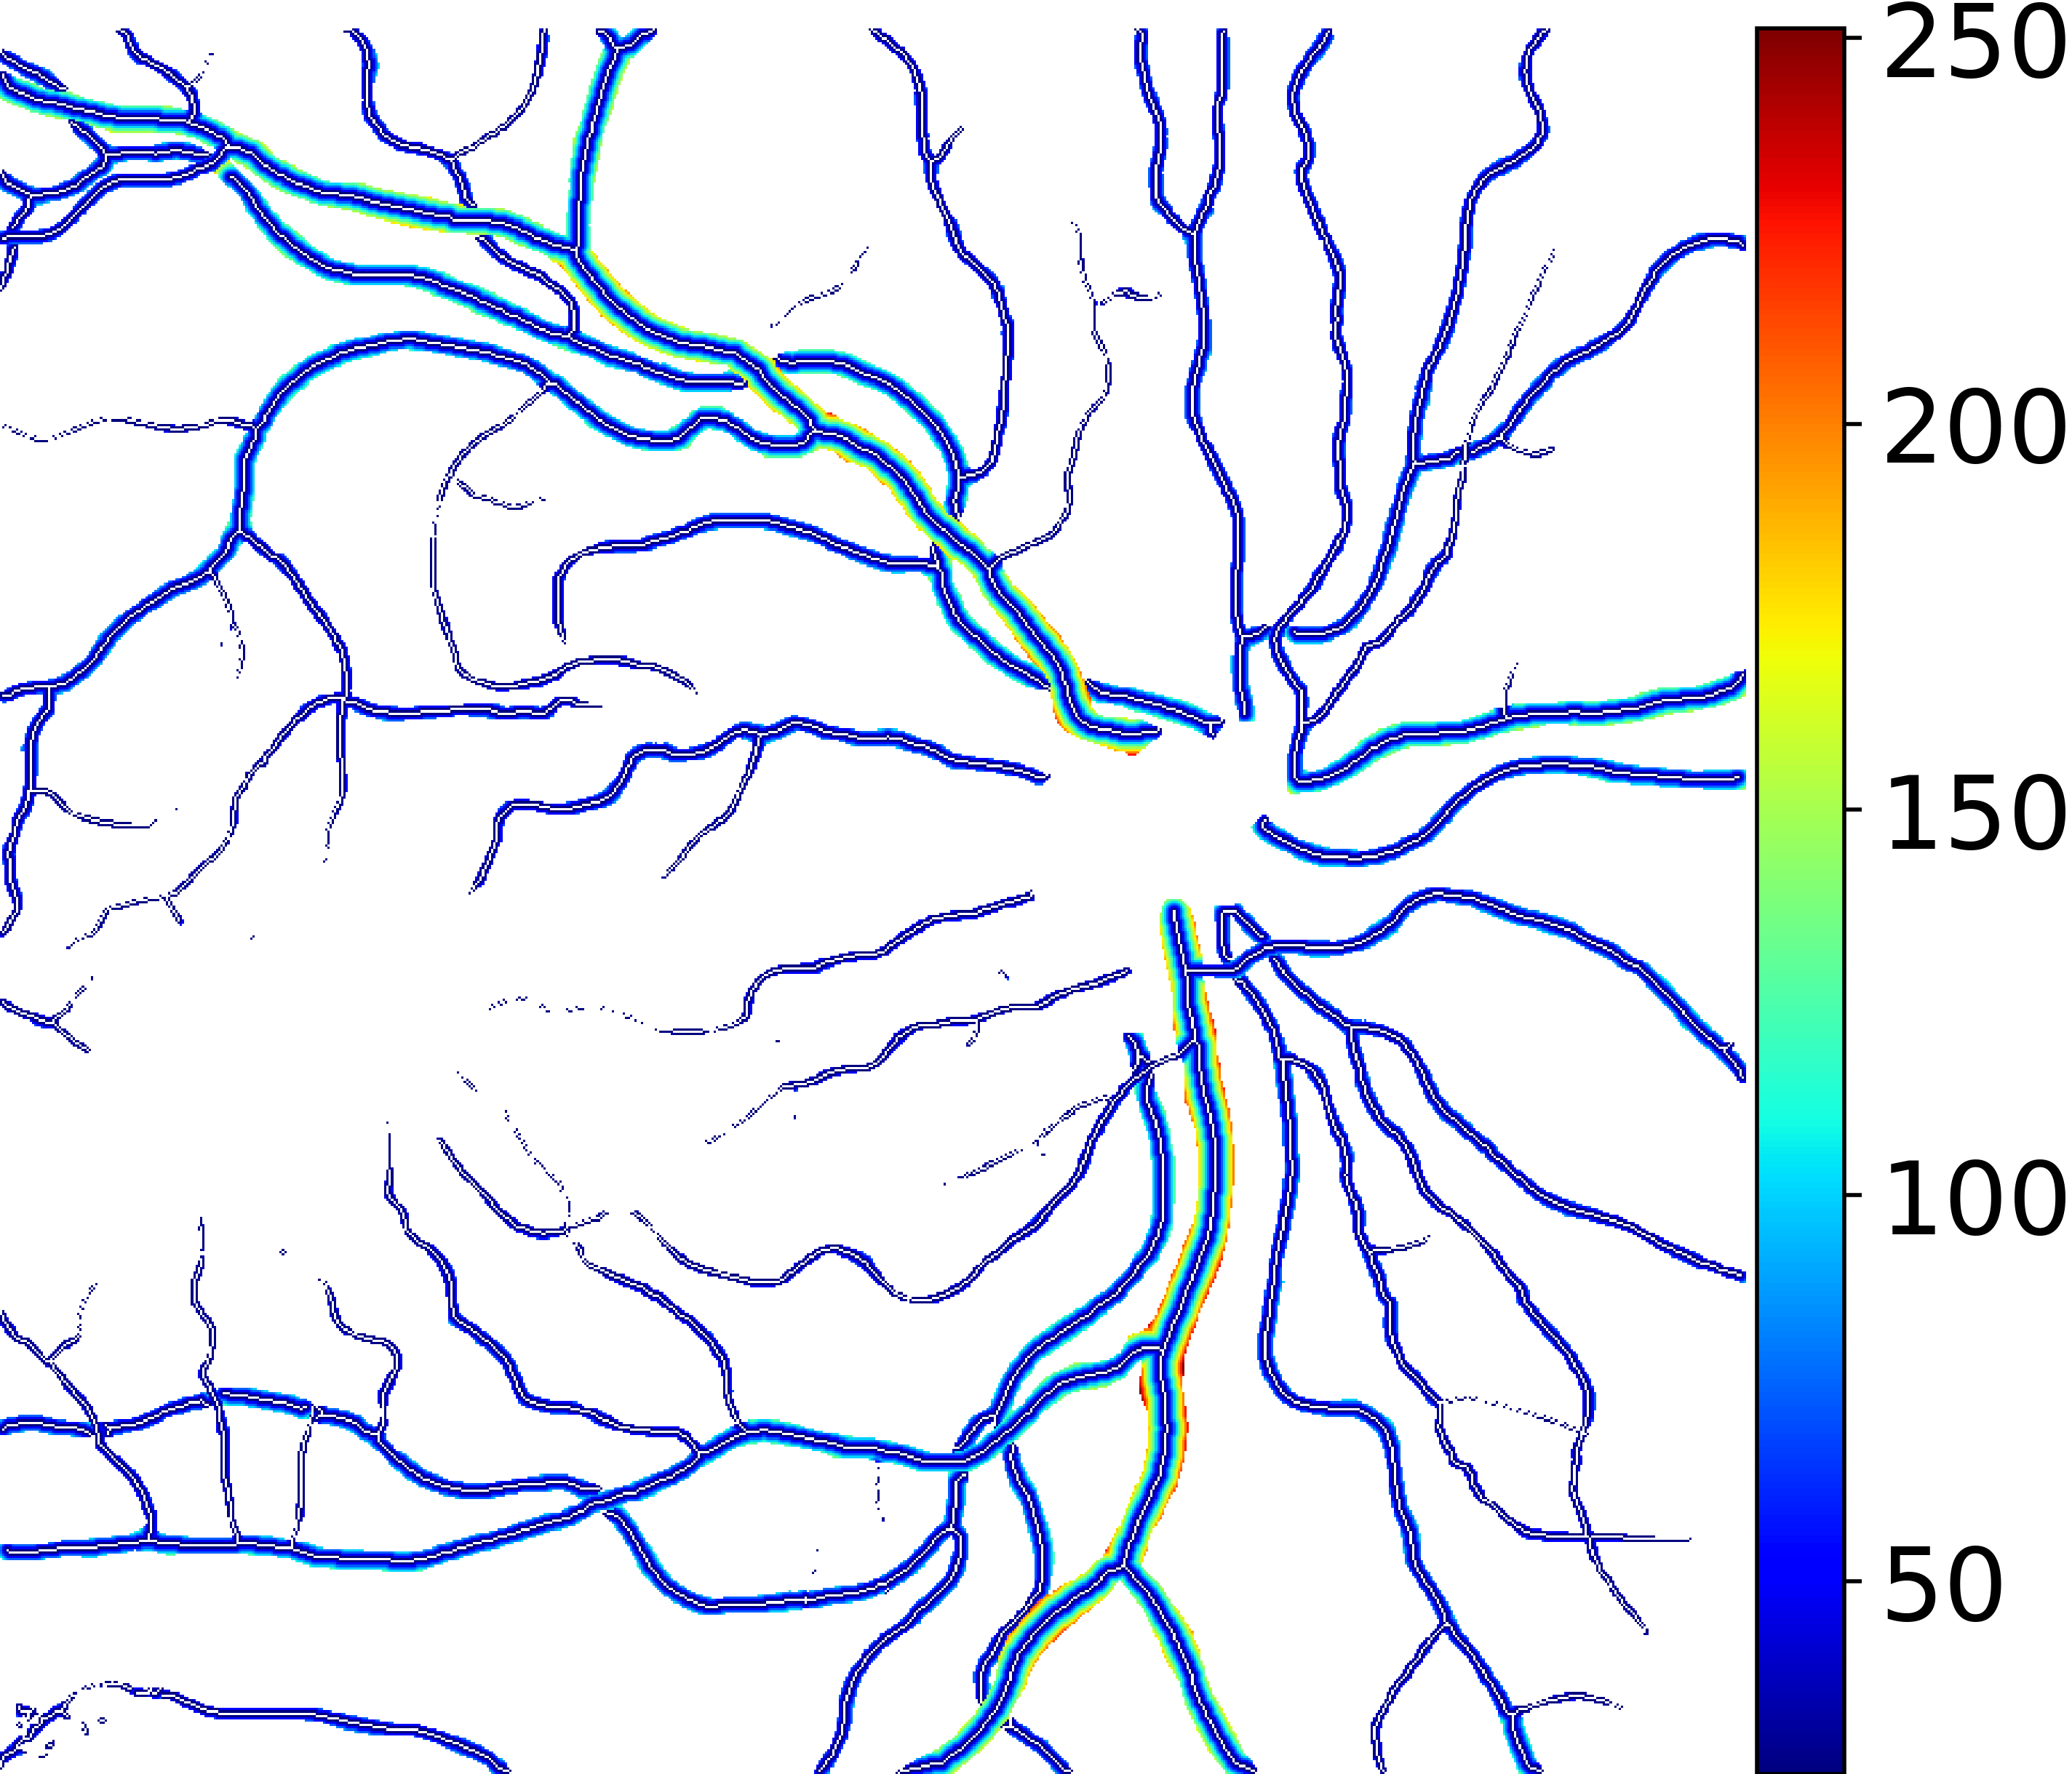

In this paper, we introduce a dataset for training deep learning CNN models to perform detailed, pixel-resolution “semantic segmentation” of Retinal Arteries and Veins in IR imaging, dubbed RAVIR. In conjunction with our new RAVIR dataset, we propose a novel deep learning-based methodology, denoted SegRAVIR, which is tailored to the semantic segmentation of retinal arteries and veins. Specifically, SegRAVIR features a two-stream encoder-decoder CNN architecture consisting of main and auxiliary streams with shared encoders to simultaneously segment the vessels and reconstruct the input images. The role of the auxiliary stream is mainly to regularize the main stream and help the shared encoder learn effective representations of the retinal vessels.

IV-A The SegRAVIR Architecture

To analyze retinal arteries and veins, we devise an encoder-decoder architecture dubbed SegRAVIR (Fig. 2), which consists of a main stream for segmenting and an auxiliary stream for reconstructing the input images. The main stream leverages residual blocks and skip connections that connect the encoder and decoder. The auxiliary stream benefits from a decoder that learns how to reconstruct the input images and acts as a regularizer. SegRAVIR’s building blocks are residual blocks consisting of two convolutional layers and an identity skip connection that adds the input of the block to the convolutional outputs. Each convolutional layer with kernel is followed by a Rectified Linear Unit (ReLU) and a batch normalization with learnable parameters and :

where and denote the input and output of the convolution layer, respectively, and , , , are pixel indices. Additionally, the output of each convolution is fed into a dropout layer for regularization. SegRAVIR’s encoder spans across 4 different resolutions, each of which consists of a residual block followed by a convolutional layer with a stride of 2 and appropriate padding to reduce the resolution of learned representations by a factor of 2. At its lowest resolution, the output of the convolution layer is fed into 3 consecutive residual blocks and then into the decoder.

SegRAVIR’s decoder has 4 corresponding resolutions consisting of transposed convolutional layers with a stride of 2 and appropriate padding to increase the resolution of learned representations by a factor of 2, followed by a residual block. At each resolution, the output of the residual blocks in the encoder is added to the output of the corresponding residual block in the decoder via a skip connection. Finally, the output of the decoder is fed into two consecutive convolutional layers with ReLU activation and batch normalization, followed by a convolutional layer with softmax activation and three output channels that correspond to background, vein, and artery classes.

Furthermore, we employ an auxiliary stream that learns to reconstruct the input images and acts as a regularizer. It is an auto-encoder that regularizes the shared encoder by learning an additional proxy task of image reconstruction in order to avoid overfitting. At each resolution, the outputs of residual blocks in the main-stream encoder are fed into a decoder that shares the same architecture as the main-stream decoder, except for the last three layers which use a convolutional layer followed by a ReLU activation function. The output of the auxiliary stream has the same size as the input image; hence, a proper image-based reconstruction loss can be employed at the original resolution.

Unlike a typical U-Net, the SegRAVIR model leverages residual blocks in both the encoder and decoder of the main stream and benefits from three residual blocks in the bottleneck of the architecture, thus enabling the capture of fine-grained details of the retinal vasculature. Moreover, its auxiliary stream regularizes the segmentation outputs, further improving performance. Fig. 2 provides additional SegRAVIR architectural details.